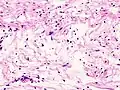

Schwannome mélanotique

C'est une tumeur rare. Elle s'intègre, dans 50 % des cas, dans le complexe de Carney (myxomes cardiaques, pigmentation lentigineuse faciale, anomalies endocriniennes). Il existe au sein de la prolifération d’abondantes mottes de mélanine ainsi que des psammomes (en). Les cellules tumorales expriment la PS100 et l’HMB45 (marqueur de différenciation mélanocytaire).

Neurinome subcutané_Antoni_B.jpg)